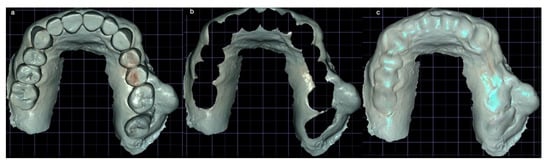

3.2. DCAI Approach Clinical Case